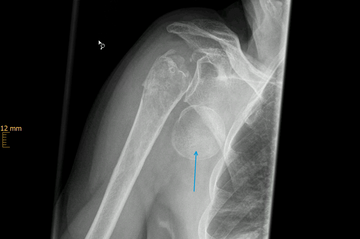

Klavikulafraktur (Schlüsselbeinbruch)

Die Klavikulafraktur ist eine typische Fraktur des jungen Patienten. Rad- und Motorradfahrer, Wintersportler und Kontaktsportler sind die typischen betroffenen Patienten.

Viele Schlüsselbeinbrüche können ohne Operation behandelt werden, wenn die Frakturstücken keine wesentliche Verschiebung (Dislokation) aufweisen. Der betroffene Arm wird in einer Armschlinge für ca. 3-4 Wochen ruhiggestellt, parallel wird mit physiotherapeutischen Behandlungen begonnen. Die Behandlungsdauer beträgt ca. 8 Wochen. Kommt es jedoch zu einer deutlichen Verschiebung der Frakturenden (um mehr als die Breite des Schlüsselbeins) und tritt dadurch eine Verkürzung oder ein Abknicken des Schlüsselbeins auf, besteht die Indikation zur Operation. Gleiches gilt auch für eine Fraktur des Schlüsselbeins mit vielen Bruchstücken (Fragmenten).